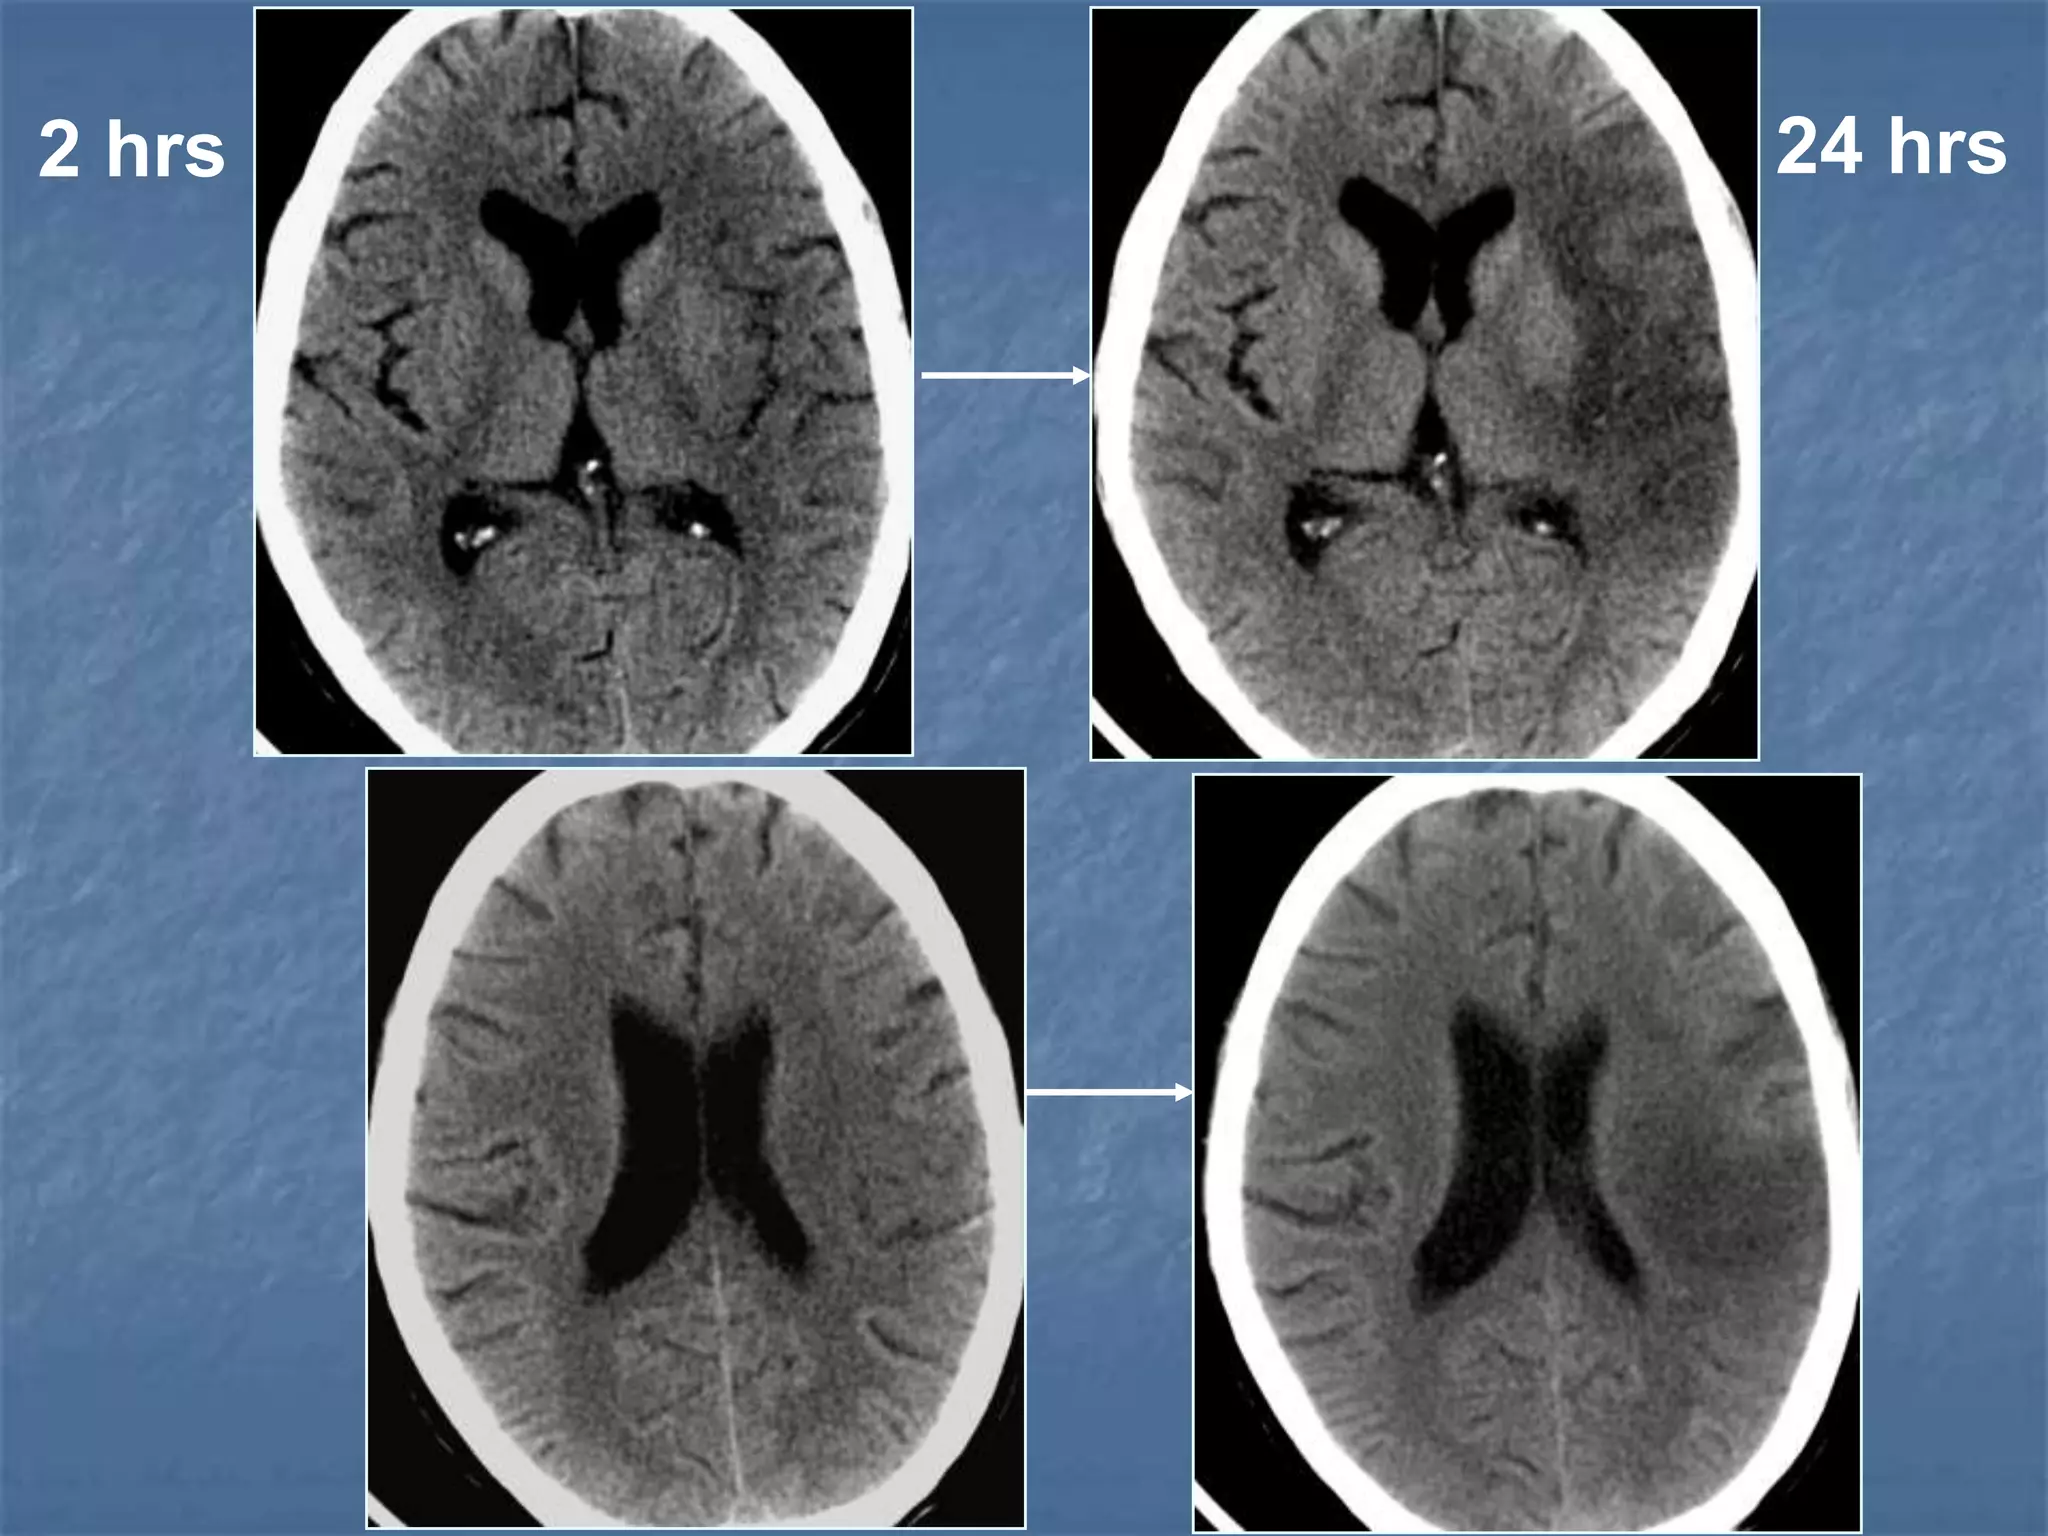

2 hrs 24 hrs

Subacute infarct (1-7 days )

 Hemorrhagic transformation in 5-40 % of all

ischemic stroke Neurology 2001; 57:1603-1610

Stroke 1999;30:761-764

CT Findings in Stroke

Hyperacute infarct (<12 hrs)

 Normal (50 to 60%)

 Hyperdense MCA

 Obscuration of lentiform nucleus

Acute infarct (12 – 24hrs)

 Loss of grey - white matter interface (insular

ribbon sign)

 Low density basal ganglia

 Sulcal effacement.

CT Findings in Stroke (Contd)…

Subacute infarct (1- 7days)

 Mass effect

 Wedge shaped hypodensity involving grey &

white matter

 Hemorrhagic transformation.

 Gyral enhancement.